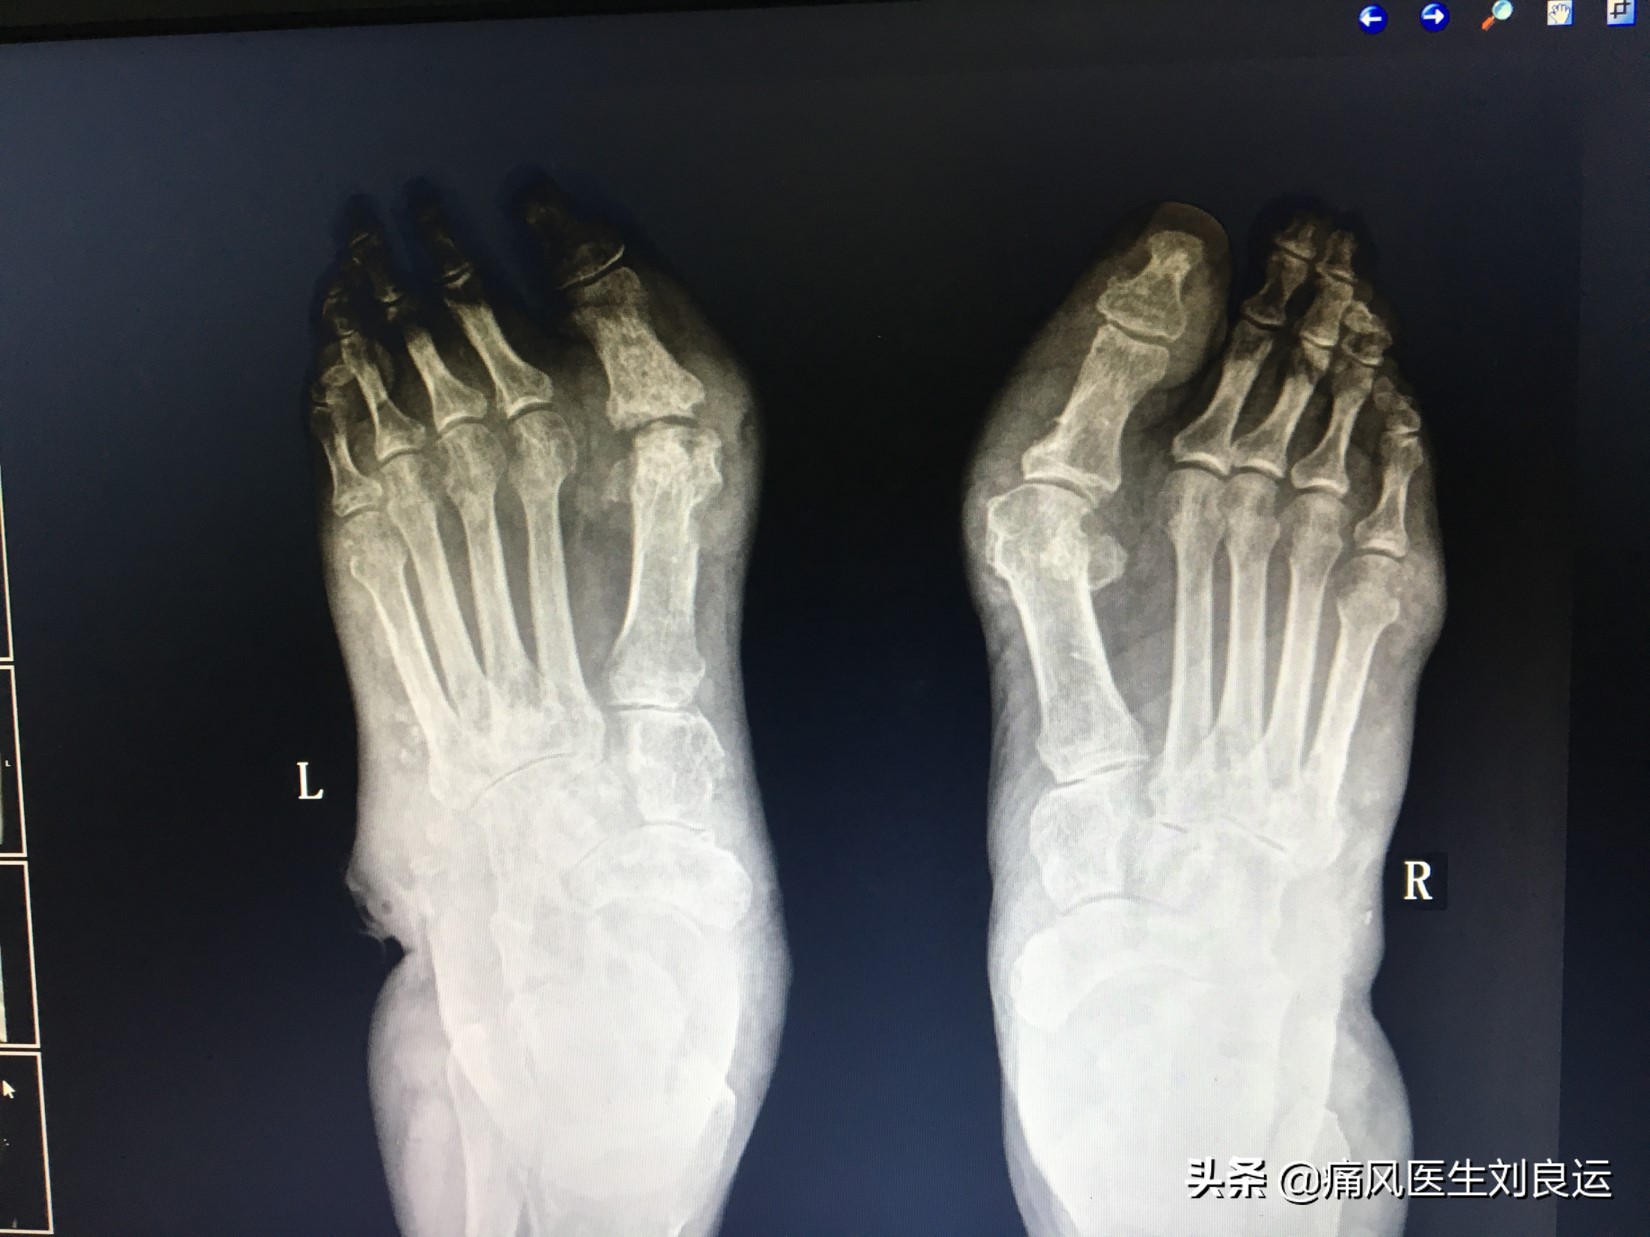

X线下双足痛风石